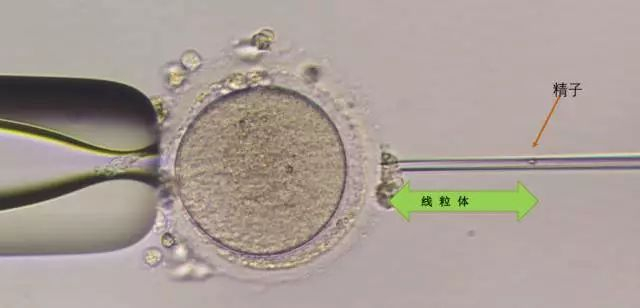

▲向卵细胞内注射线粒体及精子

在取卵当天,医生采用第二代“试管婴儿”技术(卵浆内单精子注射技术),将从骨髓细胞中提取的治疗浓度的线粒体,连同王女士丈夫的精子,一同注射进王女士的卵子中。受精卵在体外得到精心培养,顺利发育成胚胎。